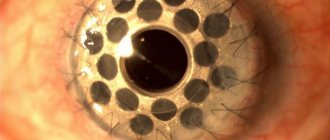

Как выглядит макулярный отек